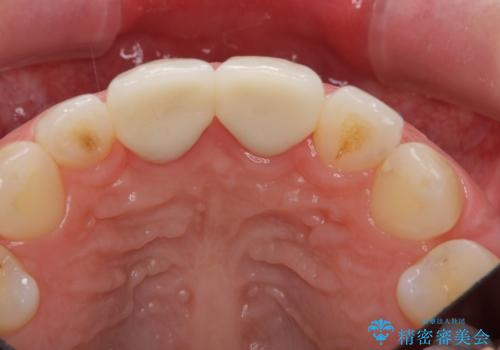

- 前歯が2本出っ歯だったのを、他院でセラミックにしたが、口元が突出しているのが治らないとのことでした。

セラミックにする際に神経をとり、無理やり歯の頭の部分のみ内側に引っ込めてありました。

出っ歯が厳しい方は、歯の頭の部分だけ被せて角度を変えても、根元は変わらないため、口元は下がりません。

もう一度前歯を元の角度に被せ直してから仮歯で矯正を行いました。

その後、マージンが舌側が深い状態だったため、歯ぐきの手術(歯周外科処置:APF)を行ってから最終的なセラミックを装着しました。